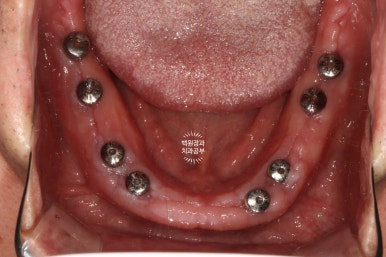

아래는 치아가 하나도 없는 상태셔서... 14개의 치아를 만들어드리기 위해 총 8개의 임플란트를 심어드렸습니다.

센스 있는 분들은 눈치채셨을 수도 있는데, 위 아래의 임플란트가 생긴게 좀 다르죠?

아래턱의 경우 뼈 상태가 워낙 튼튼하니 좋으셨고, 뼈이식이 많이 필요하지 않아 치유지대주까지 연결해드렸습니다.

즉, 위턱은 임플란트 1차수술까지 진행된 것이고 아래턱은 임플란트 1차수술,2차수술이 한 번에 모두 완료된 상태!